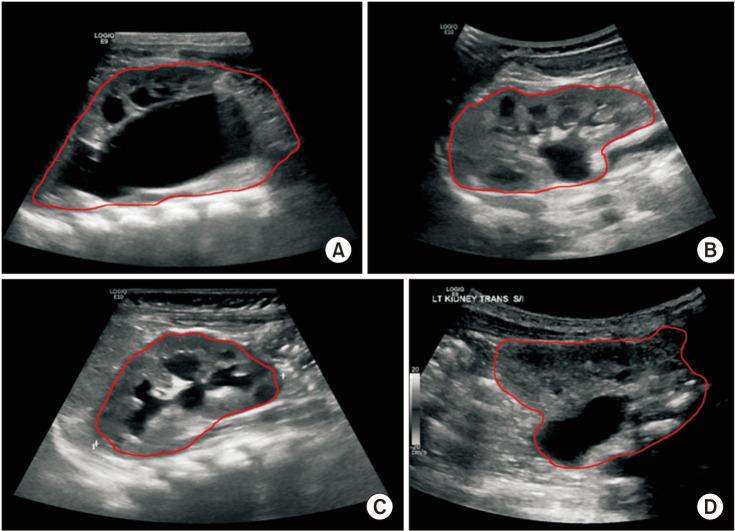

Hydronephrosis is a common pediatric urological condition, characterized by dilation of the renal collecting system. Accurate identification of the severity of hydronephrosis is crucial in clinical management, as high-grade hydronephrosis can cause significant damage to the kidney. In this pilot study, we demonstrate the feasibility of machine learning in differentiating between high and low-grade hydronephrosis in pediatric patients.

We retrospectively reviewed 592 images from 90 unique patients ages 0-8 years diagnosed with hydronephrosis at the University of Chicago's Pediatric Urology Clinic. The study included 74 high-grade hydronephrosis (145 images) and 227 low-grade hydronephrosis (447 images). Patients were excluded if they had less than 2 studies prior to surgical intervention or had structural abnormalities. We developed a radiomic-based artificial intelligence algorithm incorporating computerized texture analysis and machine learning (support-vector machine) to yield a predictor of hydronephrosis grade.

Receiver operating characteristic analysis of the classifier output yielded an area under the curve value of 0.86 (95% CI 0.81-0.92) in the task of distinguishing between low and high-grade hydronephrosis using a five-fold cross-validation by kidney. In addition, a Mann-Kendall trend test between computer output and clinical hydronephrosis grade yielded a statistically significant upward trend (p<0.001).